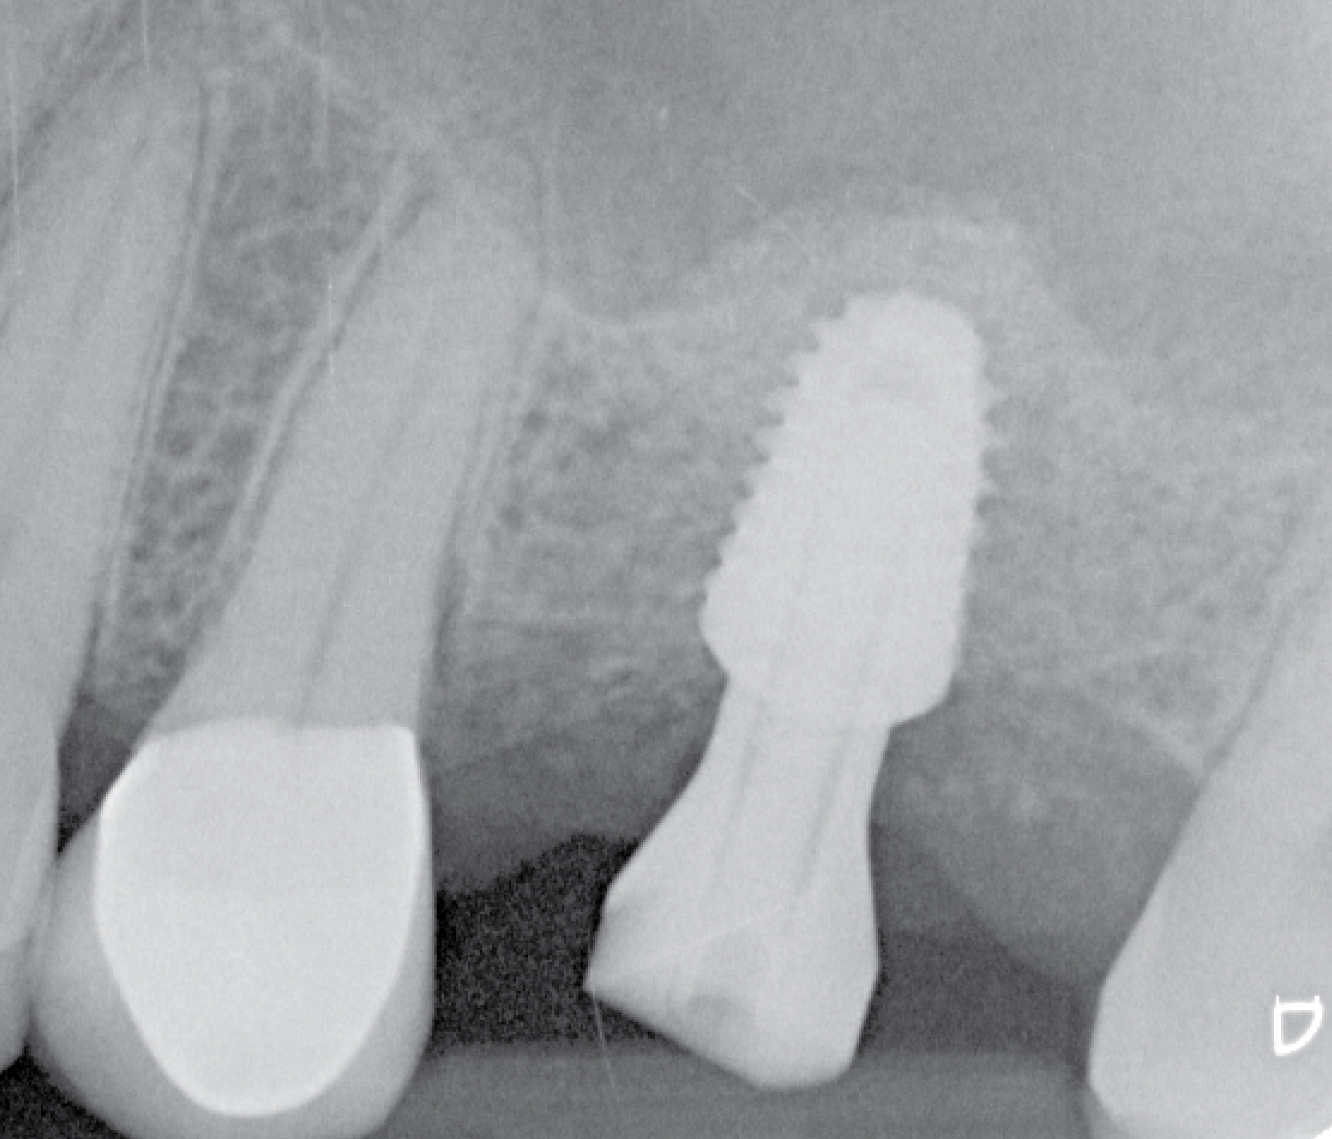

Director’s Clinical Cases

Director’s Clinical Cases